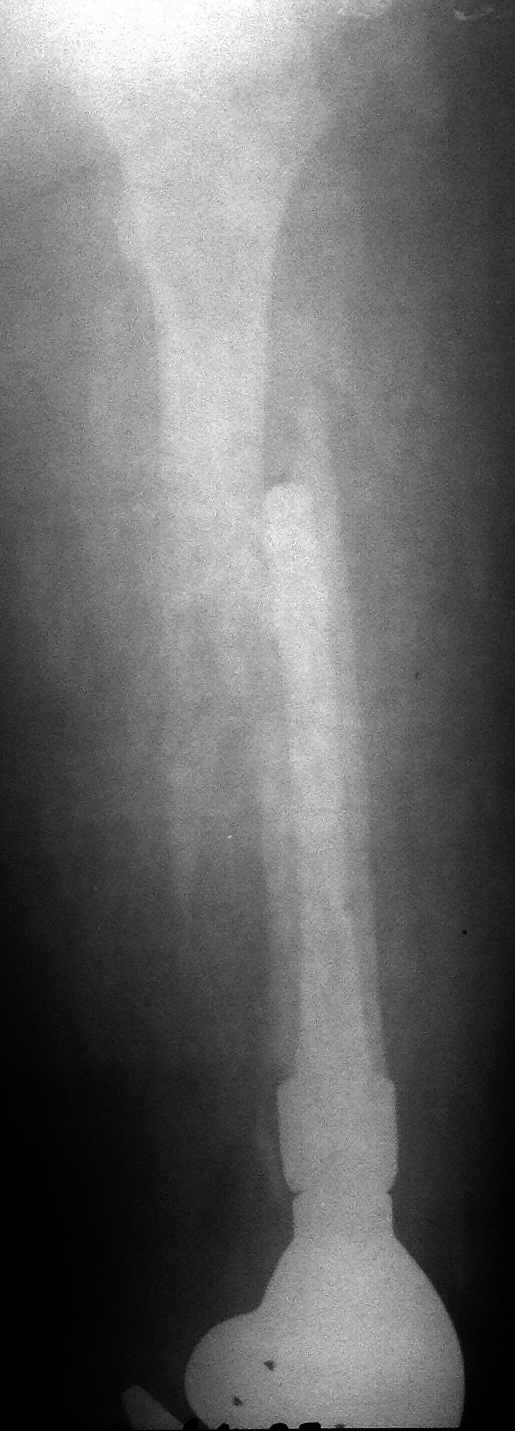

перипротезный перелом в области колена |

Молодая девушка, оперирована в 2012 году по поводу опухоли (какой не знает, выписки потеряли). Получила травму при падении. Пациентка избыточного веса. Ваша тактика? Я заранее прошу прощения за качество снимков (рентген сломаля, снималось "палатником"). Если где-то не видно - длинный спиральный перелом, ножка полностью заполняет костно-мозговой канал, цемент дошел до малого вертела.

Можно и традиционно - пластиной, и стержнем с удлинением ножки.

дискуссии похоже не получилось, выкладываю постоп снимки.

Молодцы, очень симпатично получилось. Будем надеяться на благоприятный исход.